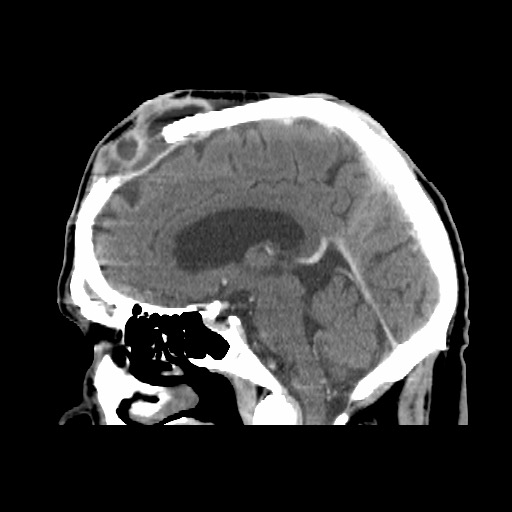

We present an 84-year-old male with advanced squamous cell carcinoma (SCC) of the scalp who had a delayed presentation for treatment (Figure 1). Prior to surgery, the patient received neoadjuvant immunotherapy with a PD-1 inhibitor. The patient’s initial operation included a 12 × 12-cm tumor excision, tangential craniectomy over the superior sagittal sinus and scalp flap based on the left temporal vessels with Integra Bilayer Wound Matrix reconstruction (Integra Life Sciences) of the scalp donor site defect (Figure 2). At the 4-month postoperative follow-up, there were concerns for recurrence of the disease. Computerized tomography scan identified a homogenous collection under the flap and moth-eaten appearance of the underlying cranium (Figure 3). The patient was taken to the operating room and found to have tumor invasion of the scalp flap, underlying bone, and dura as confirmed by frozen pathological specimen. He underwent an additional 8 × 8-cm tumor excision, partial craniectomy, and dural debridement by our neurosurgical colleagues to diminish the tumor burden (Figure 4). Wound closure was achieved by scalp flap readvancement. Negative margins were unattainable, and the patient received adjuvant immunotherapy.

Figure 3. Sagittal CT image depicting tumor recurrence.